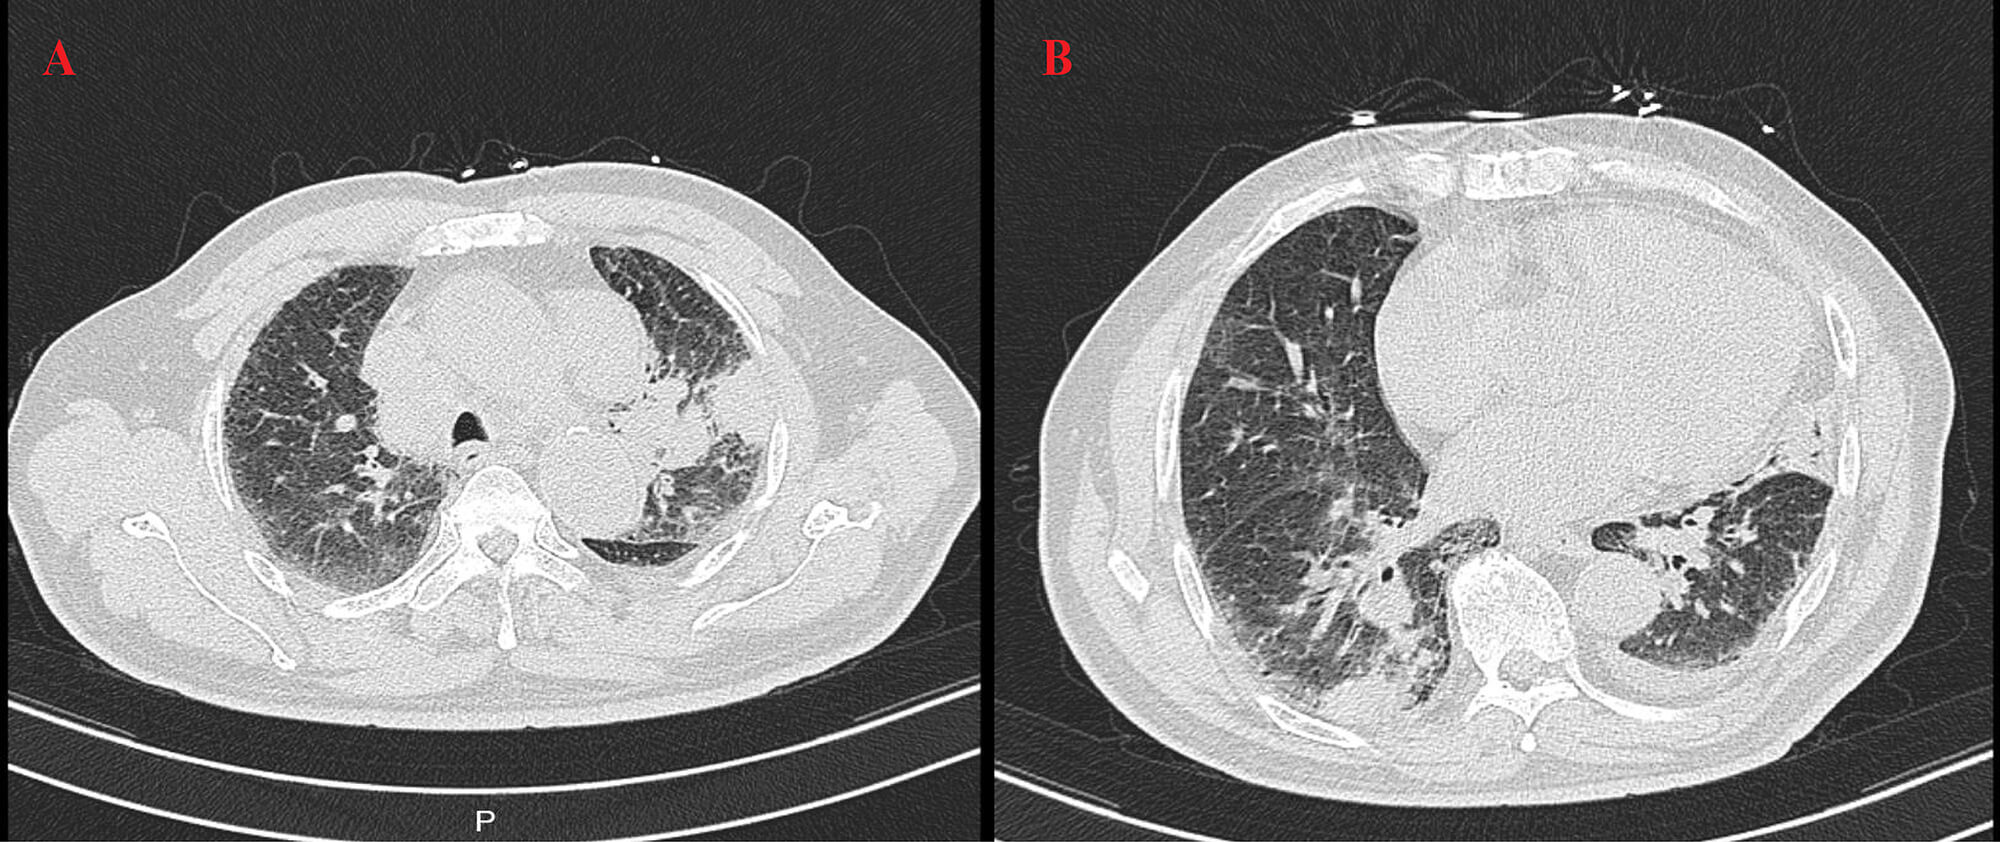

High-resolution computed tomography (HRCT) (Fig. 3) revealed patchy opacities in the left upper and right lower lobes, accompanied by multiple enlarged hilar and mediastinal lymph nodes (Fig. 4), interstitial inflammation in both lungs (Fig. 5), and a small pleural effusion. These findings were consistent with residual tumor and local progression following treatment for extensive-stage SCLC, demonstrating characteristic imaging features of SCLC.

Fig. 3.

HRCT on 23 April 2025. This chest scan showed patchy consolidation in the left upper lobe (A) and right lower lobe (B), with mediastinal lymphadenopathy.